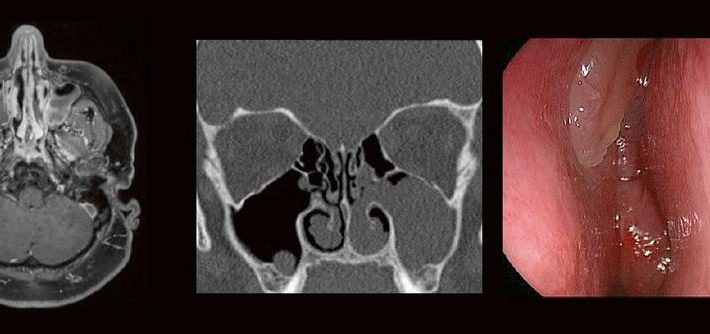

HNO & Radiologie: gemeinsam durch die NNH – ein Joint Venture (Webinar | Online)

Dr. med. André ReisbergDr. med Sebastian Plößl Die bildgebende HNO-Diagnostik macht es Anfängern nicht leicht. Die Anatomie ist komplex und weniger intuitiv als in anderen Körperregionen. Normvarianten erschweren insbesondere in den Nasennebenhöhlen den Lernprozess. Sobald pathophysiologische Zusammenhänge verstanden und wichtige klinische Aspekte verinnerlicht wurden, gelingt es einen praxistauglichen, belastbaren Befund zu erstellen. Wo muss ich […]